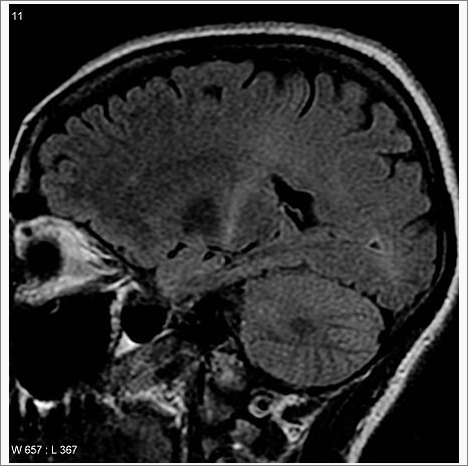

일반적으로 환자의 병력 조사와 신체 검사를 통해 초기 평가가 이루어지며, 이후 신경전도 검사(Nerve Conduction Study, NCS), 근전도 검사(Electromyography, EMG) 등의 신경학적 검사를 통해 신경 기능을 평가합니다.

필요에 따라 뇌척수액 검사나 MRI, CT와 같은 영상 검사를 통해 다른 질환을 배제하고, 루게릭병을 확진하게 됩니다.